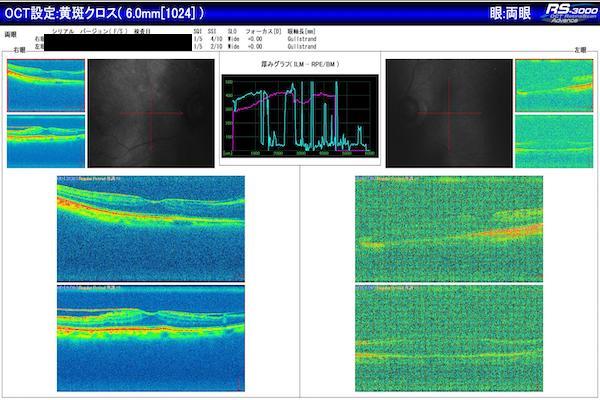

ERM は、網膜の内面に発生する薄い繊維状組織の層です。人々はそれらを黄斑しわと呼ぶこともあります。 ERM は通常、自然な老化によって発生し、75 歳以上の人に発症​​することがほとんどです。小児でも発症することがありますが、これはまれです。

ERM は通常、老化の自然なプロセスの一部として発生します。網膜の内面全体に発生するこれらの薄い膜は、通常、症状を引き起こしません。ただし、視覚の歪みや視力の低下を引き起こす可能性があります。